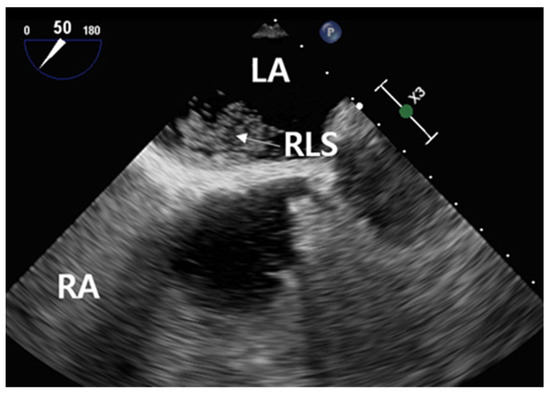

2.2.1. Cardiac Testing

2.2.3. Contrast-Enhanced Transesophageal Echocardiography